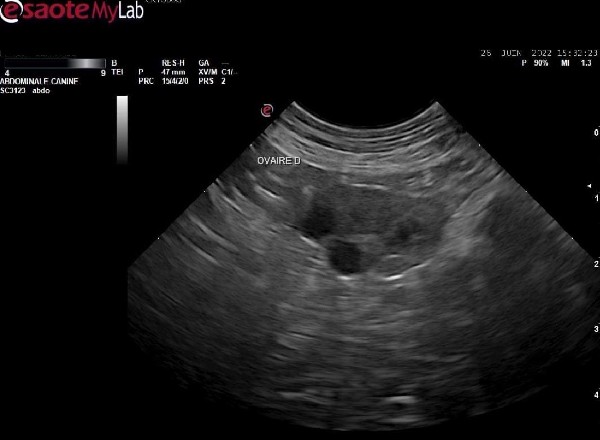

- Réalisation d'une échographie ovarienne, complémentaire au dosage de progestérone pour déterminer la date d'ovulation.